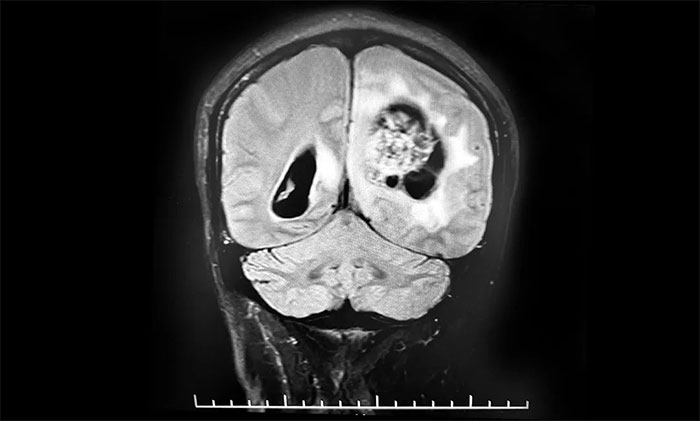

頭顱MRI平掃+增強+DWI+MRA提示,左側(cè)頂枕葉巨大腫瘤伴局部瘤卒中,幕上腦室系統(tǒng)、腦干受壓變形,中線結(jié)構(gòu)右移19mm,大腦鐮下疝形成。李士其教授等專家團隊會診指出,患者腦內(nèi)巨大占位,性質(zhì)不明,并且患者已經(jīng)發(fā)生腦疝昏迷,生命危在旦夕,應(yīng)盡快進行手術(shù)治療,挽救患者生命,同時明確病理診斷。

▲ 左側(cè)頂枕葉巨大腫瘤伴局部瘤卒中